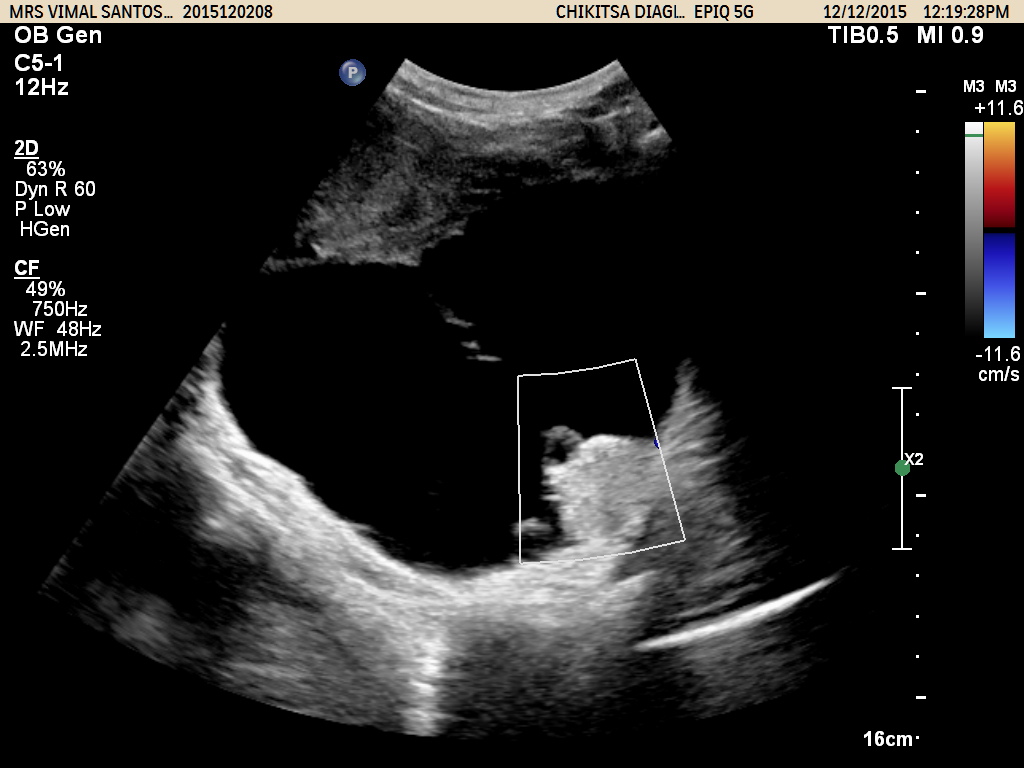

Gynaec Doppler Study

This is indicated in cases of ovarian tumors, suspected vascular malformations of the uterus, varicosities in the vagina and pelvis etc. A decision to use doppler may be taken during a regular pelvic ultasound examination.